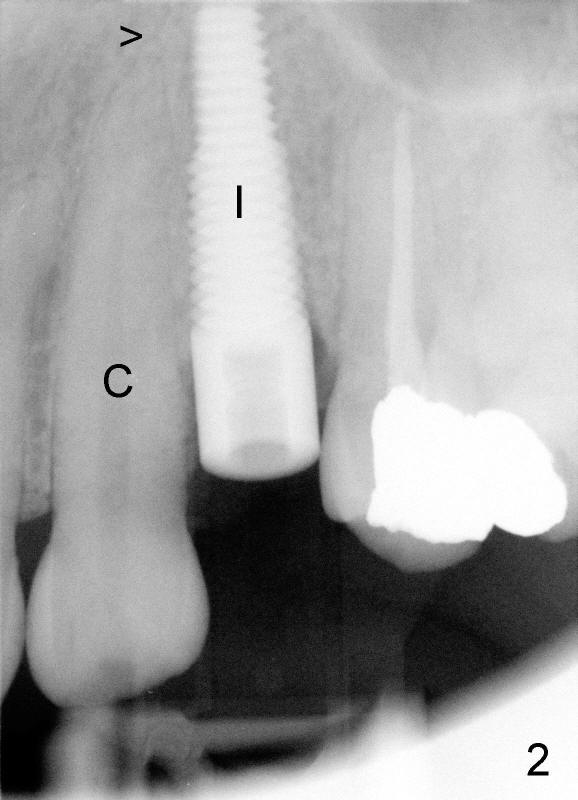

柳小姐口腔卫生不是很好,我们做立刻植牙,植牙又暴露在口腔,应该使用抗菌素,但是最重要决定因素却是病人坚决要求使用,她理由是十年前,患牙(上颌第一双尖牙)引起严重尖牙间隙感染,不过根管治疗后,一直没有疼痛,植牙术前根尖片显示根管冲填尚可,根尖阴影很小(图一:箭头),好像不至于造成术后感染。最后还是使用抗菌素。病人一直很紧张,术后第二第三天她打电话说:尖牙间隙又肿胀了,我们安慰她:可能是因为手术创伤所致,为了取得初步植牙稳定,植牙(图二:I)比尖牙(C:箭头指向尖牙根尖)还长,随访几天后,病人肿胀慢慢减轻。其实抗菌素对于这个病例很重要,为什么呢?仔细分析图一,你可能猜出几成。